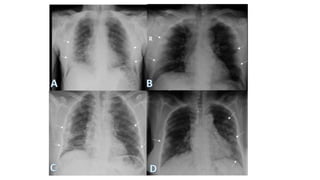

RUL RML

RUL Bronchopneumonia

• #22 Chest radiograph (A) shows a bilateral reticulonodular pattern. High-resolution computed tomography (CT) image at the level of the main bronchi (B) demonstrates bilateral ground-glass opacities and centrilobular nodules (arrows). High-resolution CT scan at the level of the basal segmental bronchi (C) shows centrilobular nodules (straight arrows), branching opacities (tree-in-bud pattern; curved arrow), ground-glass opacities, small foci of consolidation, and mild thickening of the interlobular septa (arrowheads). The patient was a 20-year-old man with Mycoplasma pneumoniae pneumonia.